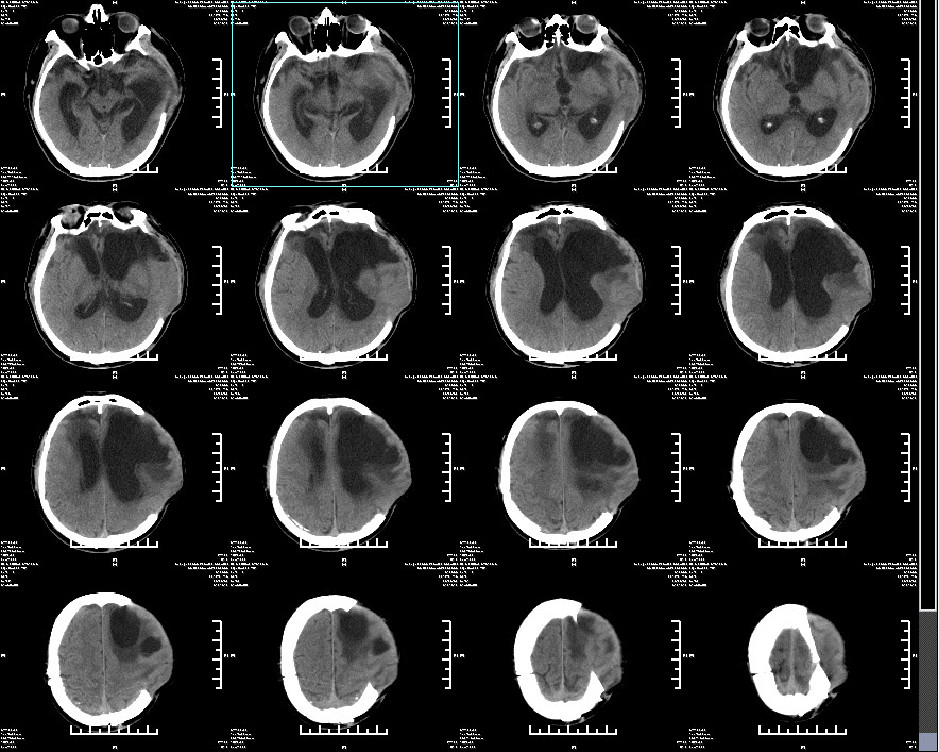

现病史:患者于入院前2小时因外伤后出现神志不清,恶心呕吐,反应迟钝,答非所问,口鼻流血,肢体无力,无肢体抽搐及寒颤高热,致本院急诊救治,头颅CT示:左额颞急性硬膜下血肿;双额颞脑挫伤;创伤性蛛网膜下腔出血;颅底骨折;颅腔积气;急诊予止血、脑保护等对症治疗措施,检查治疗期间,患者意识不清进一步加重,呼之不应,呕吐胃内容物,收入院进一步手术治疗。专科查体:昏迷, GCS 1-2-3 6分,左瞳5mm,对光反射缺失,右瞳3mm,对光反射存在,四肢痛刺激屈曲,病理征阴性。

入院诊断:双额颞脑挫伤、左额颞创伤性硬膜下血肿、创伤性蛛网膜下腔出血、颅底骨折、创伤性脑疝、左顶额骨骨折、右顶枕骨骨折。

急诊行左侧额颞顶去骨瓣减压术+血肿清除术+颅内压监护探头置入术。术后ICP6-9mmHg。

术后常规复查头颅CT(2019年1月15日9点54分):右顶硬膜外出血急诊行右顶硬膜外血肿清除术。

二次术后常规复查头颅CT(2019年1月15日16点04分)